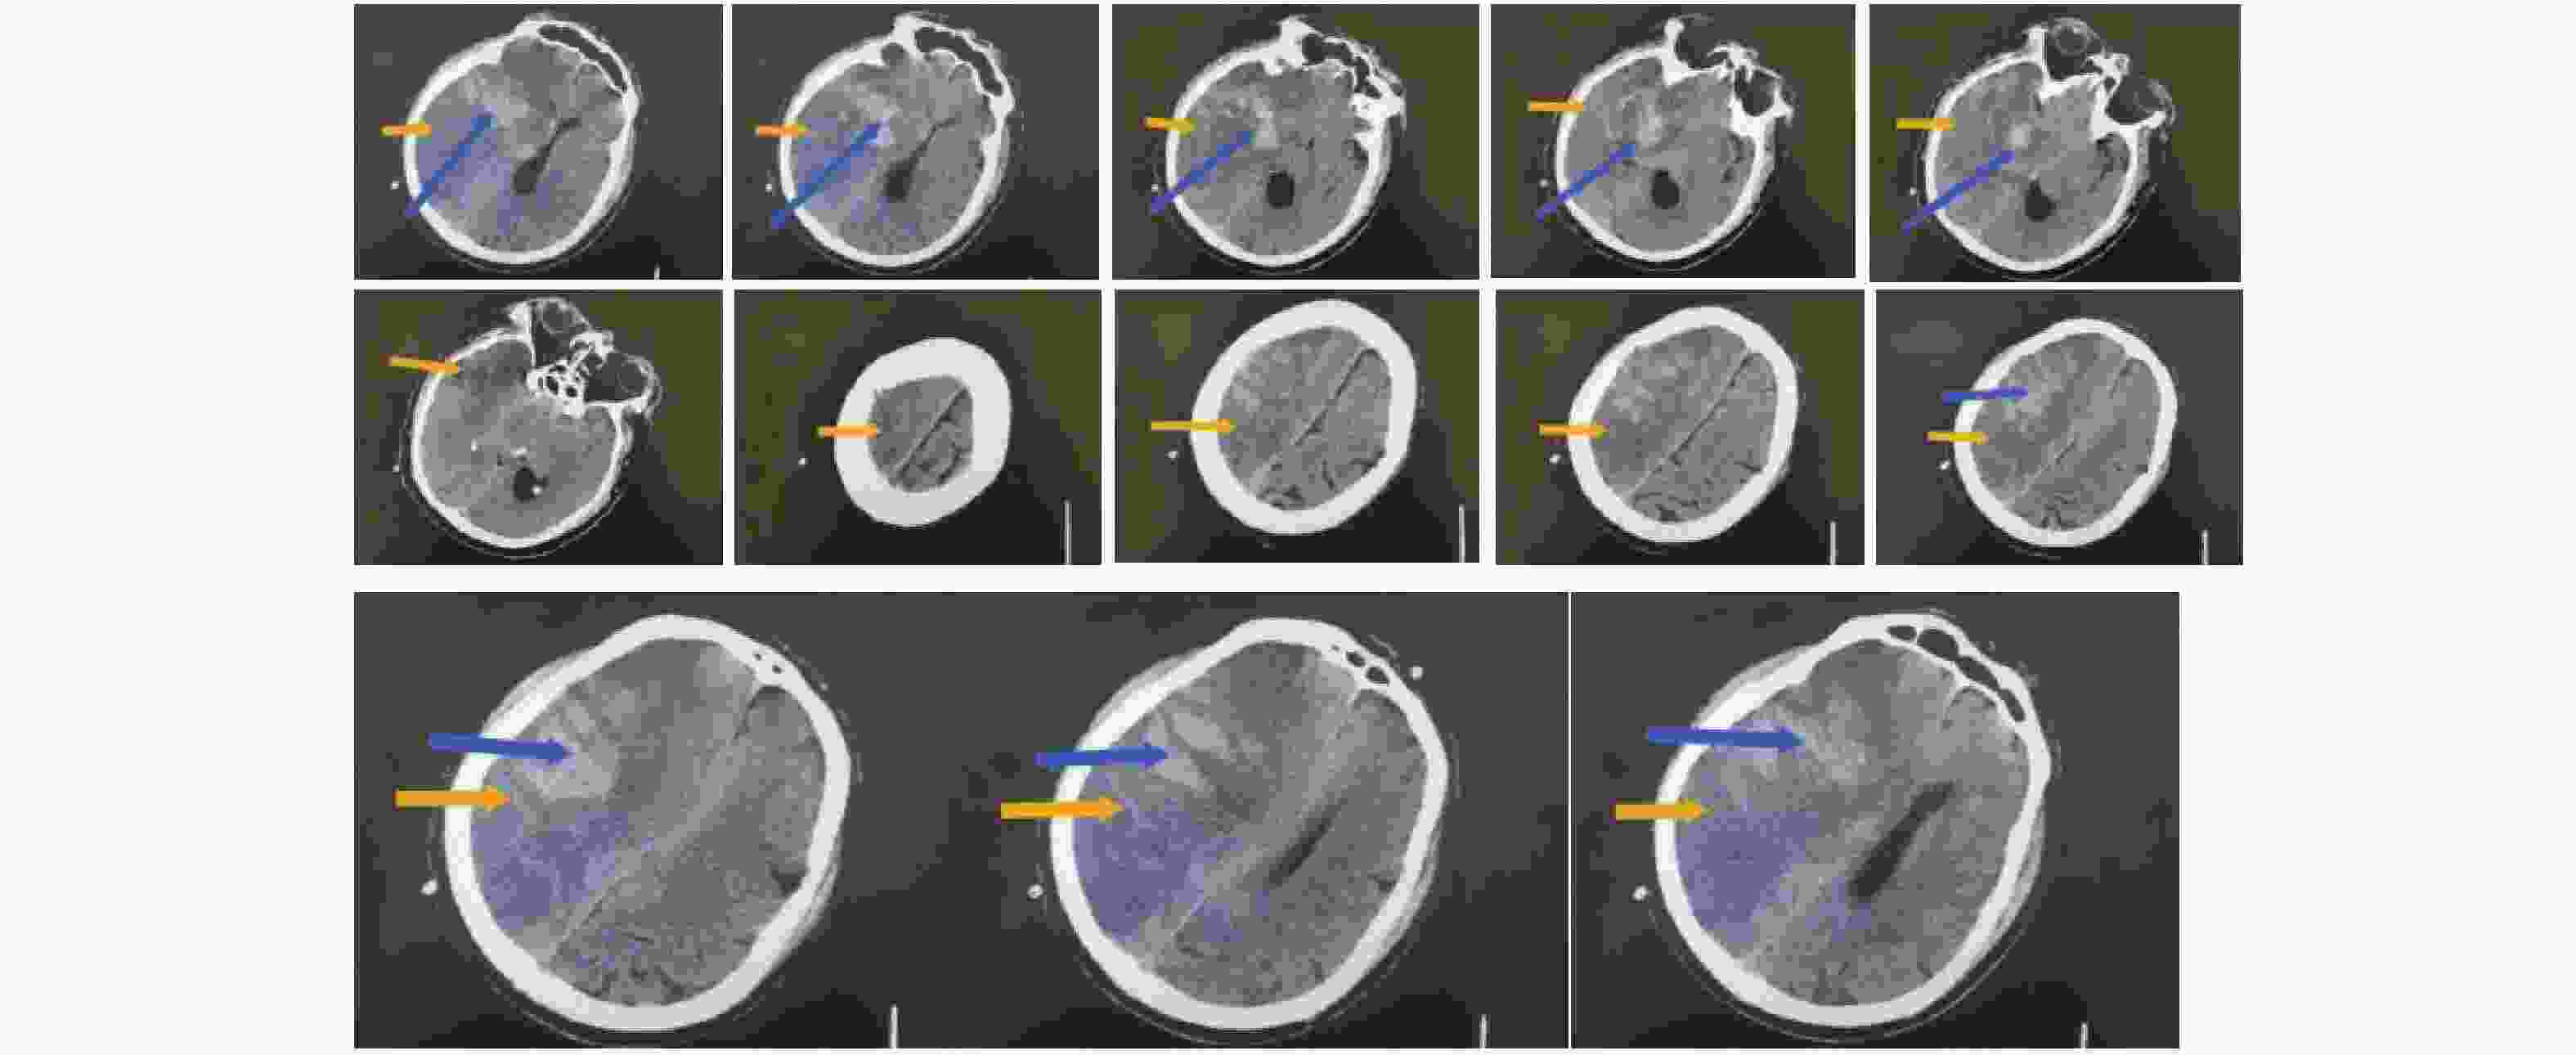

图  2  良好组术前头颅影像学表现

注:男性患者,75岁,从CT上看右侧额叶、颞叶、顶叶、岛叶大面积脑梗塞伴出血,中线左移。其中橙色箭头指向低密度区为梗塞区,蓝色箭头指向较高密度区为出血。

Figure  2.  Preoperative cranial imaging findings in the good outcome group